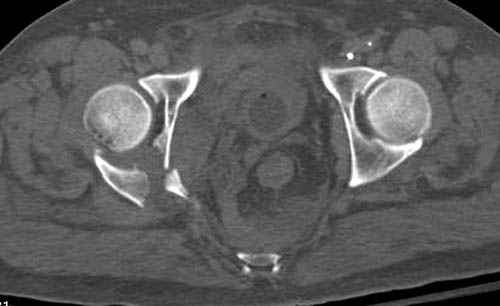

По возможности вышлите снимки, сканы таза до

реконструкции, интраоперационные.

По снимку создается впечатление о высоком поперечном переломе, задней колонны, стенки; почему не пользовались *magic screw*?

Снимки здесь....